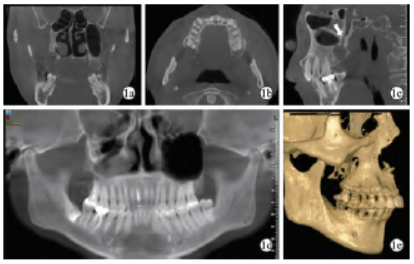

入院时专科检查:颜面部对称,张口度为三横指,17牙合面见牙色充填物,边缘龋坏,不松动,右侧上颌骨后部呈术后改变,牙槽骨较对侧低平(图1),颊侧及远中黏膜稍红肿,前庭沟周围可见术后瘢痕,未见瘘口,未扪及波动感,无乒乓球样感。CBCT示:17冠部高密度影及髓腔,根管内未见根充物影像,17远中可见大小约16mm×14mm×10mm椭圆形低密度影,边界清晰,可见骨白线,毗邻腭大管,右侧上颌窦术后改变,位置高,窦腔小(图1)。

图1 囊肿术前CBCT影像。1a:冠状面;1b:矢状面;1c:水平面(白色箭头为翼腭管);1d:曲面断层;1e:三维重建